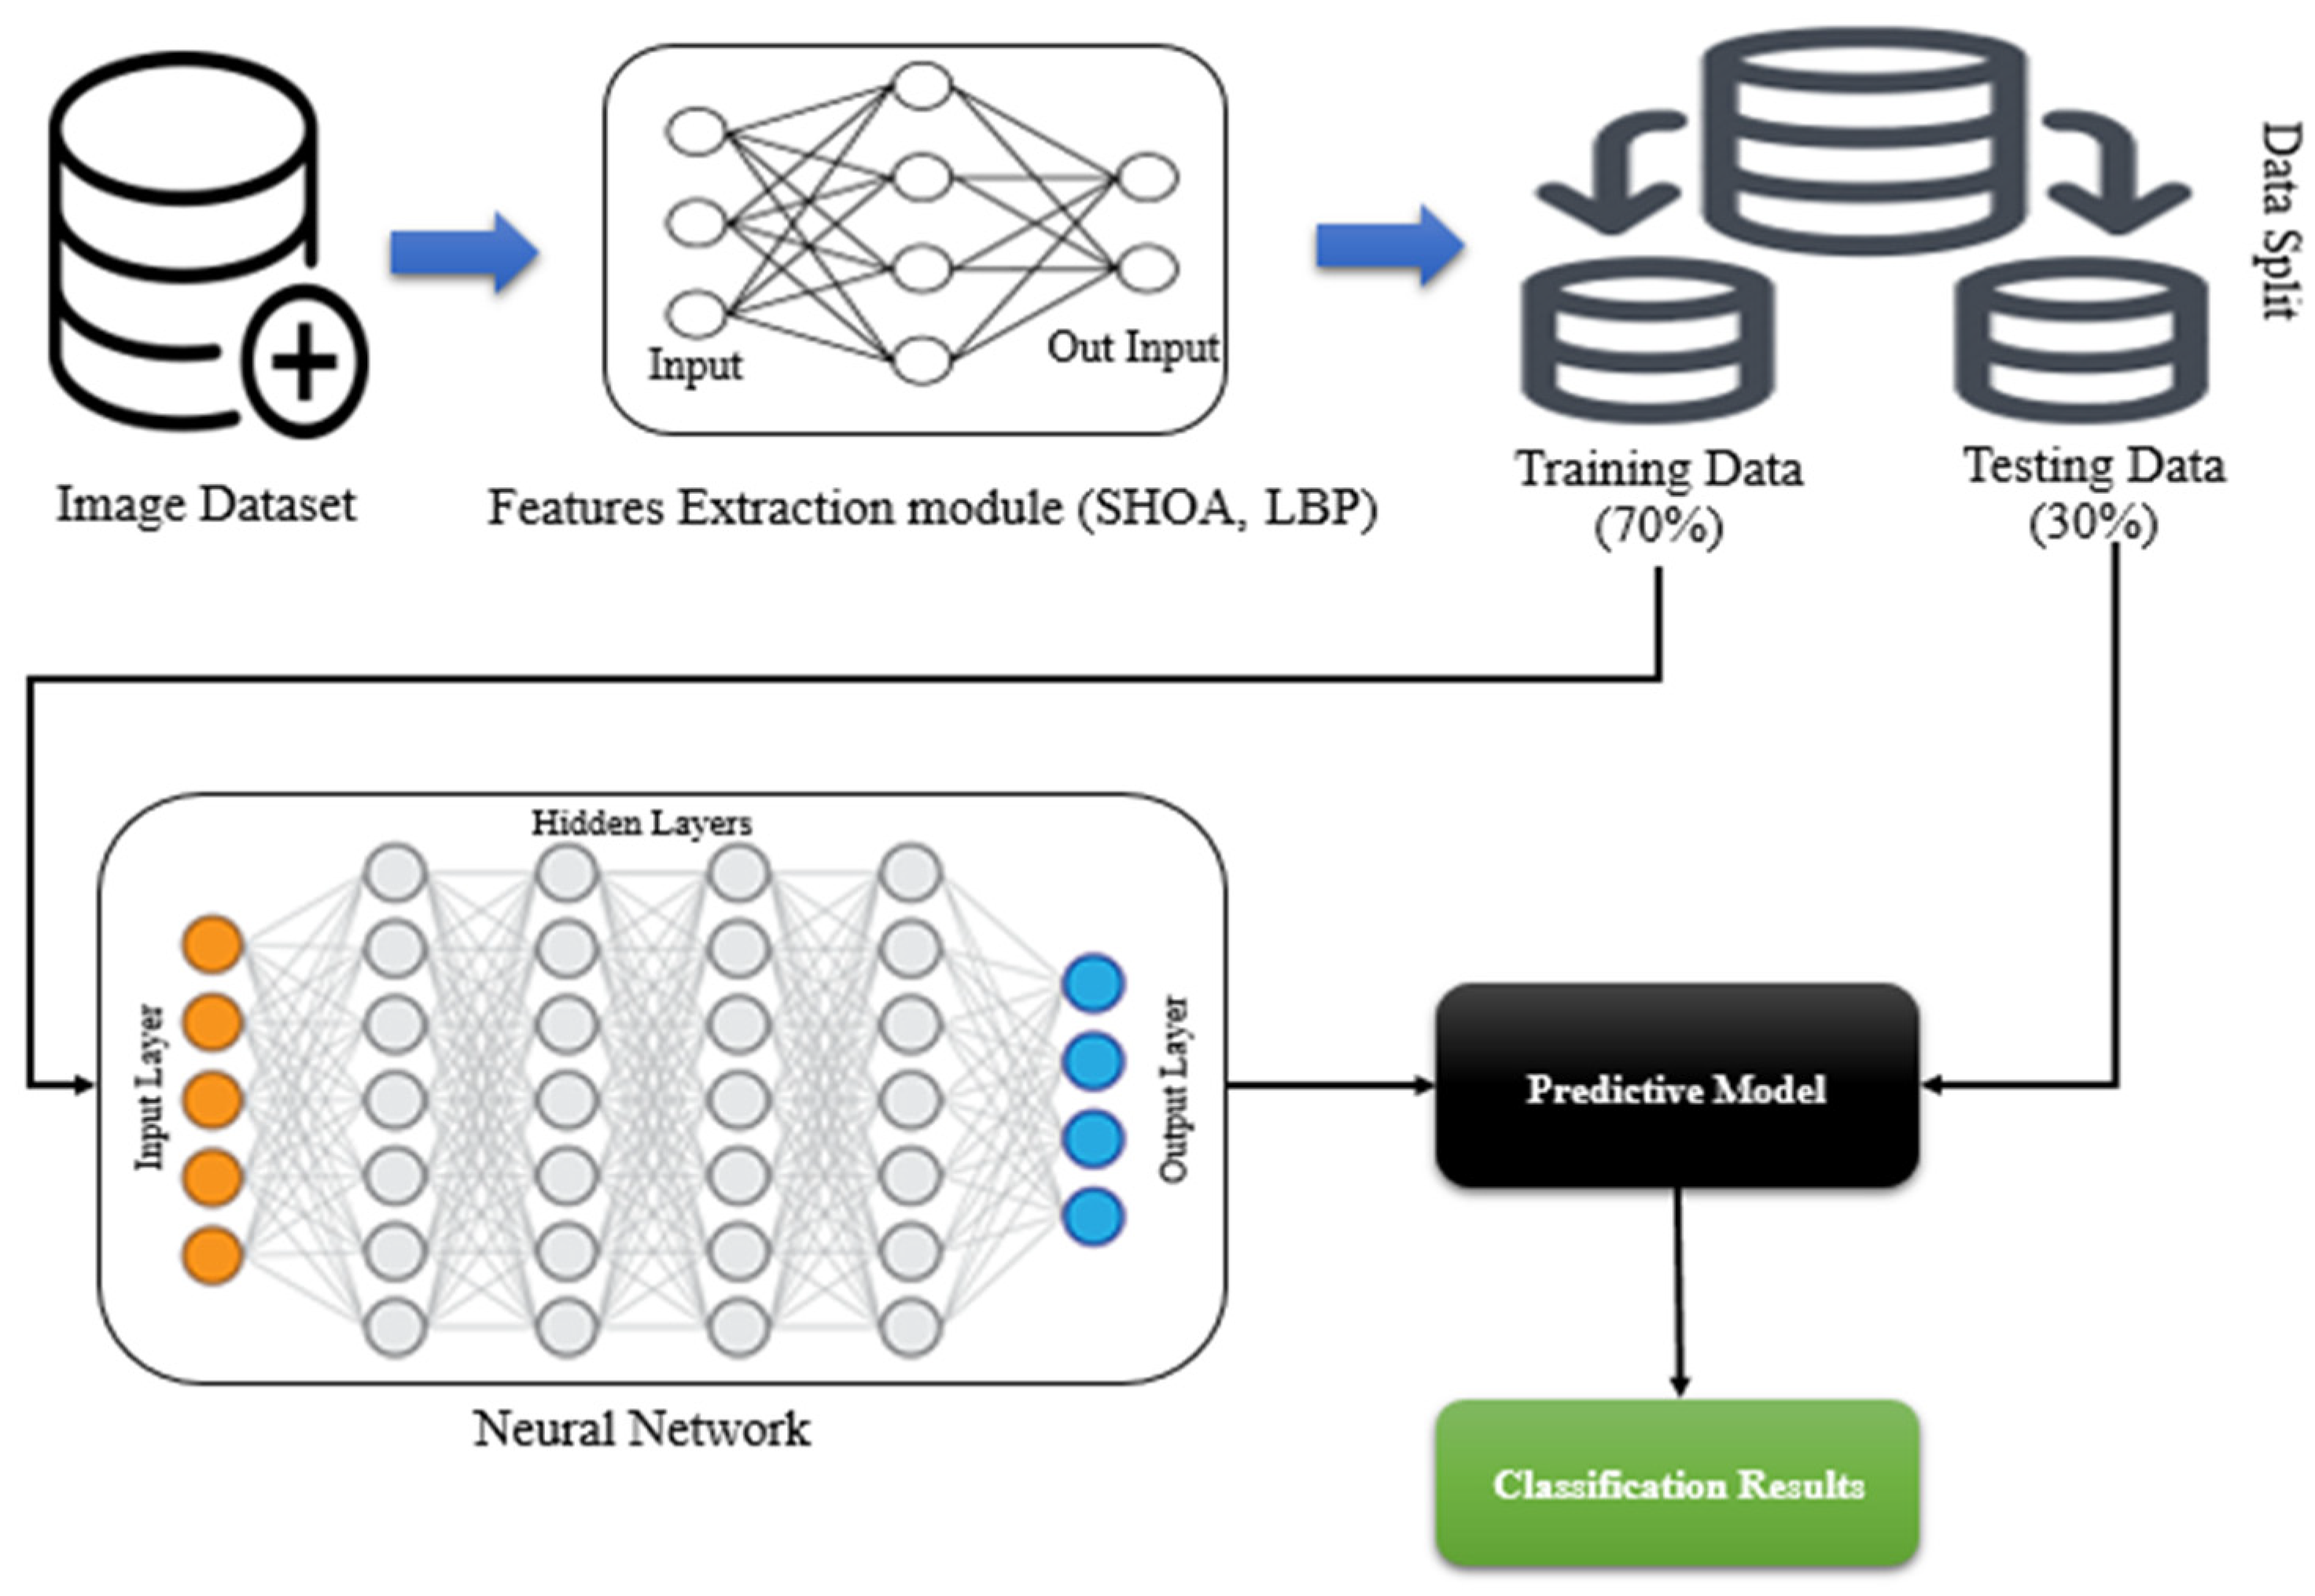

3.2. Optimization of Features Using the SHOA Algorithm

3.3. CNN and GRU-Based Lung Nodule Classification

4.1. Performance Evaluation Using Training and Testing Data with Distinct Classes